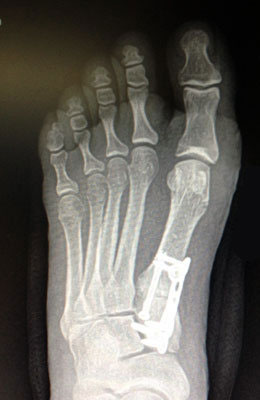

Before

Lapidus Forever Bunionectomy™ before

After

Lapidus Forever Bunionectomy™ after

Lapidus Forever Bunionectomy™

Jamie is a 53-year-old nurse who was having trouble with pain in her foot and arch and a painful bunion. Our Lapidus Forever Bunionectomy™ was utilized to correct her bunion and to stabilize her foot, arch and of course big toe joint. Jamie was back at work at 10 weeks post-surgery with full function and no pain (she didn’t even take an anti-inflammatory like ibuprofen).